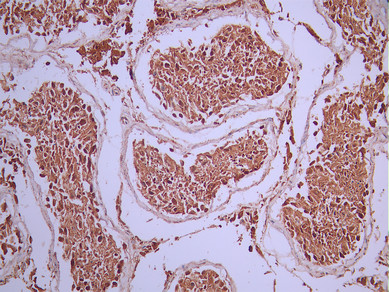

IHC image of CSB-RA252590A0HU diluted at 1:100 and staining in paraffin-embedded human testis tissue performed on a Leica BondTM system. After dewaxing and hydration, antigen retrieval was mediated by high pressure in a citrate buffer (pH 6.0). Section was blocked with 10% normal goat serum 30min at RT. Then primary antibody (1% BSA) was incubated at 4°C overnight. The primary is detected by a Goat anti-rabbit polymer IgG labeled by HRP and visualized using 0.05% DAB.